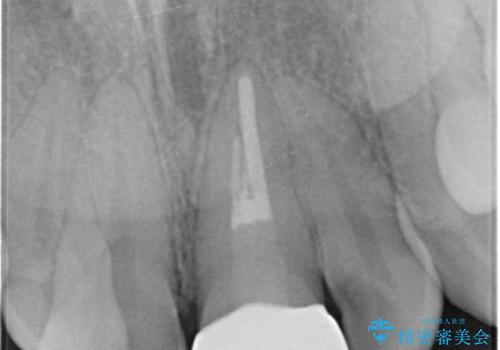

根の治療のやりかえは希望されなかったので土台だけやりかえを行い、ジルコニアクラウンで治療を行いました。

- ジルコニアクラウンスタンダード・仮歯・ファイバーコア 18.7万円費用は治療当時の料金となります